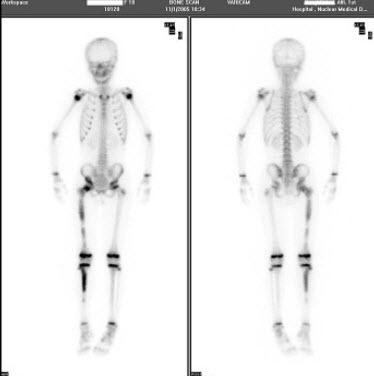

85、单项选择题

女,12岁,诉右下肢疼痛1周,体检无肿块,行全身骨显像如图,可能的诊断是()

A.大致正常的骨影像

B.右股骨远端骨肉瘤征象

C.右股骨骨髓炎

D.右下肢软组织蜂窝炎

E.右股骨头缺血坏死